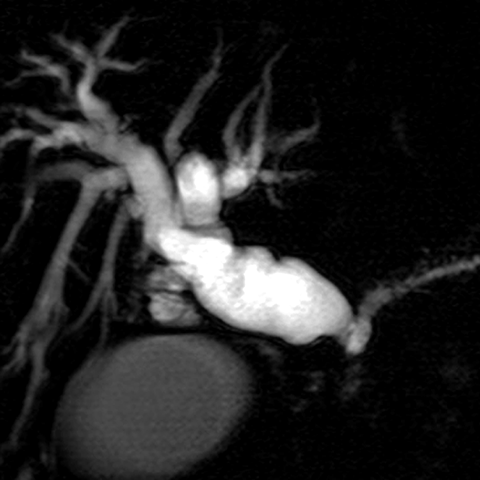

56 year-old male presents with painless jaundice [7 of 7]